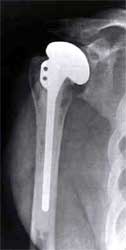

假体过大,假体位置肱骨近段截骨不足,肱骨头过高,引起疼痛活动受限。

翻修手术后,肱骨近段进一步截骨,更换小号肱骨头,矫正肱骨头过高